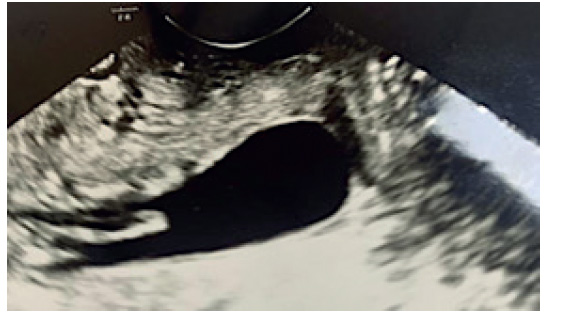

La ecografía obstétrica abdominal de control evidenció un feto en presentación podálica con bienestar normal. Por ecografía transvaginal, la longitud del cérvix era de 2,8 cm con dilatación del orificio cervical interno, cuyo vértice estaba en el canal cervical (figura 1). En un control ecográfico posterior se observó la retracción cervical, con una longitud del cérvix de 2,5 cm y el orificio cervical interno cerrado.

Figura 1 ecografía transvaginal a las 24 semanas de gestación, donde se evidenció cuña cervical con dilatación del orificio cervical interno y protrusión de las membranas por el orificio cervical externo.